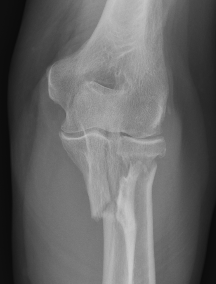

Simple Monteggia fracture - dislocations

Definition

Proximal ulna / olecranon fracture

- posterior radial head dislocation most common in adults

- no fractures

Bado Type II most common in adults with posterior radial head dislocation